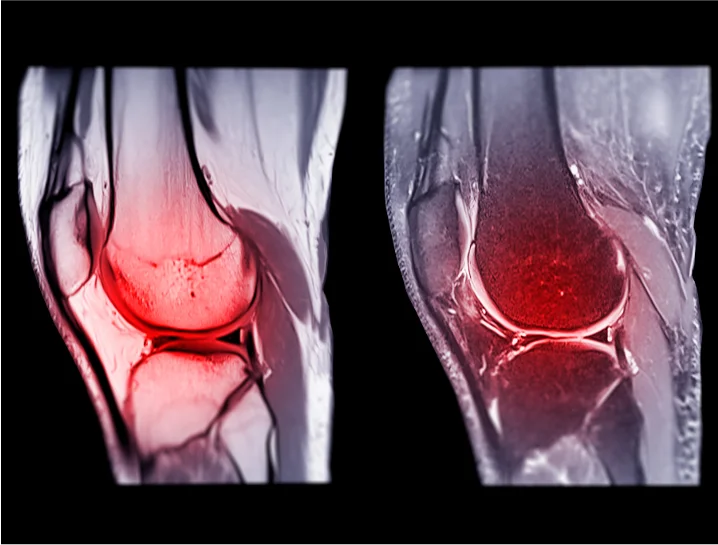

3. Imaging Tests

Imaging tests are vital in diagnosing an ACL tear and determining the extent of the injury.

- X-rays – Used to rule out fractures or other bone-related injuries that might occur alongside the ACL tear.

- Magnetic Resonance Imaging (MRI) – Provides detailed images of soft tissues, including the ACL, to confirm the tear's severity and assess for additional damage to the meniscus, cartilage, or other ligaments.